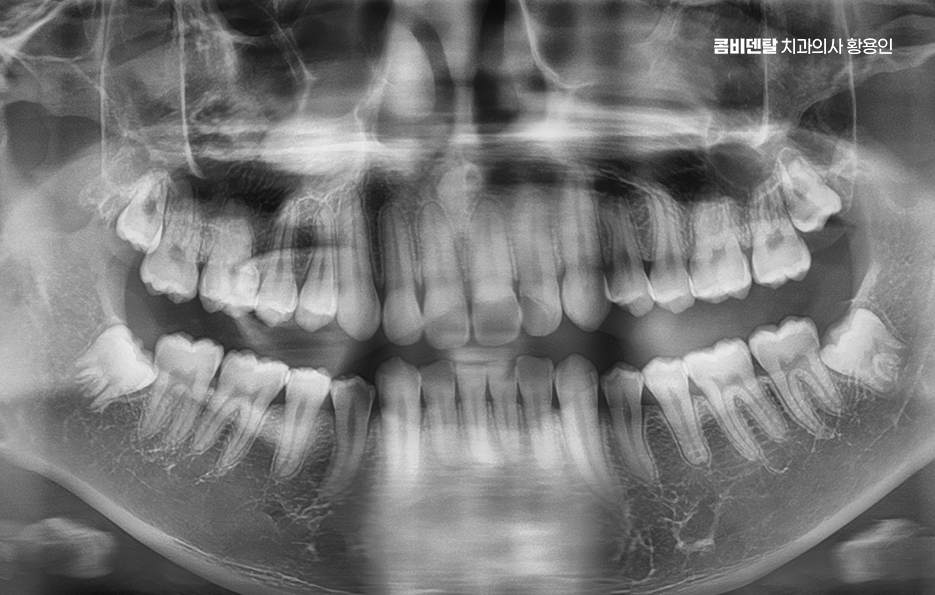

출처 아카이브 열기완전매복사랑니라는 단어 자체가 참 낯설게 느껴졌어요, 처음에는 그게 무슨 말인지조차 몰랐고, 단순히 사랑니라는 건 그냥 어금니 맨 끝에 나중에 나오는 이 정도로만 알고 있었어요 누구나 한 번쯤은 뽑는 거니까 나한테도 언젠간 그런 일이 생기겠지 하면서도, 사실 딱히 깊이 고민해본 적은 없었어요, 그런데 어느 날 왼쪽 아래 턱 깊숙한 곳이 묘하게 욱신거리고, 무언가 불편한 느낌이 계속되더라고요, 딱히 부어오르거나 겉으로 드러난 문제는 아닌데, 먹을 때마다 이상하게 한쪽으로는 씹기 싫고, 가만히 있을 때도 잇몸 깊은 곳에서 묵직한 압력이 느껴지는 기분이었어요, 그게 몇 주째 반복되니까 이제는 그냥 넘길 수 없겠다는 생각이 들어서 치과에 가게 됐어요. 진료를 받고, 엑스레이를 찍고, 설명을 듣는데, 그제야 알게 된 게 바로 완전매복사랑니라는 이름이었어요, 내 사랑니는 겉으로는 전혀 드러나지 않았지만, 잇몸과 뼈 안쪽 깊숙이 누운 채로 누워 있었고, 그것도 똑바로 난 게 아니라 옆 어금니 방향을 향해 비스듬히 자라고 있다는 것이었죠. 문제는 사랑니 발치도 까다로울 수 있고 주변 치아나 잇몸에도 영향을 줄 수 있다는 점이었어요

이처럼 사랑니 발치에 대해서는 언젠가 정도로 생각하시는 분들이 많지만 막상 통증이 느껴질 즈음이 되면 발치에 대한 막막함을 느끼게 되는 경우가 많으며 특히 완전매복사랑니 발치 같이 다소 고난도의 발치 케이스에 해당한다면 당장 대학병원부터 예약해야 할지 지켜봐야 할지 걱정하시는 분들이 많이 있는데요

완전 매복사랑니는 말 그대로 잇몸 속에 완전히 묻혀 있는 사랑니를 말하며 겉으로 보이질 않기 때문에 문제가 없는 것처럼 느껴지기도 하지만 실제로는 겉으로 안 보인다는 이유만으로 안심할 수 없으며 오히려 잇몸 속 깊숙이 들어가 있기 때문에 문제가 생겼을 때 더 큰 통증이나 합병증으로 이어질 수 있는 게 바로 완전 매복사랑니의 특징이라 할 수 있었어요

완전 매복사랑니는 보통 아래턱, 즉 하악의 뒤쪽에서 자주 발견되는데 위턱보다는 아래턱 뼈가 더 단단하고 구조적으로 복잡해서 발치 난이도가 더 높을 수 있으며 이 매복된 사랑니는 위치나 각도에 따라서도 발치의 난이도가 달라질 수 있었어요

여기에 더해서 신경과의 거리도 문제로 아래턱에는 하치조신경이라는 굵은 감각신경이 지나가는데 완전 매복사랑니의 뿌리가 이 신경과 가까이 위치해 있는 경우가 많아서 만약 발치 중 이 신경을 건드리거나 손상이 생기면, 입술이나 턱 끝 부위에 감각 이상이 생길 수 있어요.

완전매복사랑니 발치 그래서 무조건 바로 뽑는다고 되는 게 아니라, 사전에 정밀한 진단과 영상검사가 꼭 필요하며 일반적인 파노라마 사진 외에도 CT 촬영을 통해 신경과의 거리, 뿌리의 형태, 턱뼈의 두께 등을 정밀하게 확인해야 발치 계획을 안전하게 세울 수 있었어요.